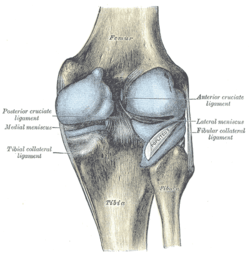

Ligaments

The ligaments surrounding the knee joint offer stability by limiting movements and, together with the menisci and several bursae, protect the articular capsule.

Intracapsular

The knee is stabilized by a pair of cruciate ligaments. The anterior cruciate ligament (ACL) stretches from the lateral condyle of femur to the anterior intercondylar area. The ACL is critically important because it prevents the tibia from being pushed too far anterior relative to the femur. It is often torn during twisting or bending of the knee. The posterior cruciate ligament (PCL) stretches from medial condyle of femur to the posterior intercondylar area. Injury to this ligament is uncommon but can occur as a direct result of forced trauma to the ligament. This ligament prevents posterior displacement of the tibia relative to the femur.

The transverse ligament stretches from the lateral meniscus to the medial meniscus. It passes in front of the menisci. It is divided into several strips in 10% of cases.[15] The two menisci are attached to each other anteriorly by the ligament.[17] The posterior and anterior meniscofemoral ligaments stretch from the posterior horn of the lateral meniscus to the medial femoral condyle. They pass posteriorly behind the posterior cruciate ligament. The posterior meniscofemoral ligament is more commonly present (30%); both ligaments are present less often.[15] The meniscotibial ligaments (or "coronary") stretches from inferior edges of the mensici to the periphery of the tibial plateaus.

Extracapsular

The patellar ligament connects the patella to the tuberosity of the tibia. It is also occasionally called the patellar tendon because there is no definite separation between the quadriceps tendon (which surrounds the patella) and the area connecting the patella to the tibia.[18] This very strong ligament helps give the patella its mechanical leverage[19] and also functions as a cap for the condyles of the femur. Laterally and medially to the patellar ligament the lateral and medial retinacula connect fibers from the vasti lateralis and medialis muscles to the tibia. Some fibers from the iliotibial tract radiate into the lateral retinaculum and the medial retinaculum receives some transverse fibers arising on the medial femoral epicondyle. [8]

The medial collateral ligament (MCL a.k.a. "tibial") stretches from the medial epicondyle of the femur to the medial tibial condyle. It is composed of three groups of fibers, one stretching between the two bones, and two fused with the medial meniscus. The MCL is partly covered by the pes anserinus and the tendon of the semimembranosus passes under it.[8] It protects the medial side of the knee from being bent open by a stress applied to the lateral side of the knee (a valgus force). The lateral collateral ligament (LCL a.k.a. "fibular") stretches from the lateral epicondyle of the femur to the head of fibula. It is separate from both the joint capsule and the lateral meniscus.[8] It protects the lateral side from an inside bending force (a varus force). The anterolateral ligament (ALL) is situated in front of the LCL.

Left knee-joint from behind, showing interior ligaments.